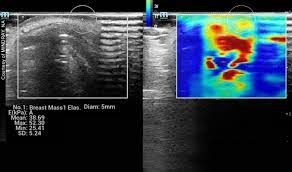

Pathological Views of Dense Breast Tissue

Ultrasound offers a supplemental scan and peace of mind in its ability to find the pathology and almost instantaneously distinguishes a benign cyst from a possible or definite cancer